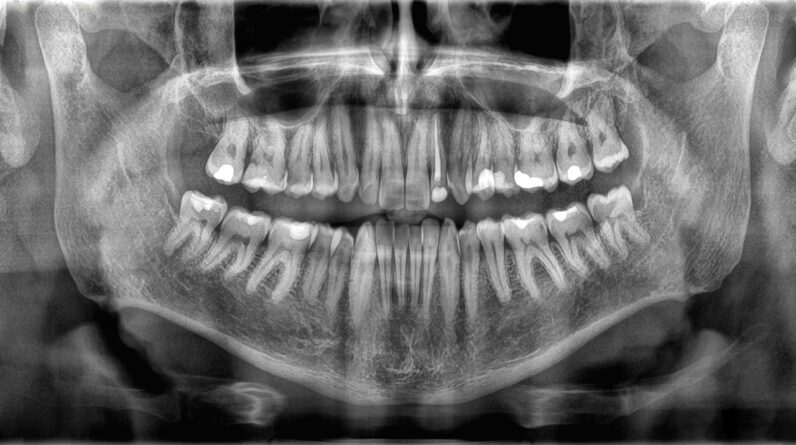

Structure of teeth and bonesDue to the fact that bones and teeth do various tasks, they’re likewise constructed in a different way. The external structure of teeth is called enamela thin layer of mineralized tissue. Enamel is the hardest compound in the body– a home it obtains from loaded crystals made from a substance of calcium and phosphate.

Beneath the enamel lies dentin, a kind of mineralized tissue that’s somewhat softer than enamel however still tough. Dentin comprises most of a tooth’s structure, and it consists of small tubes that hold capillary and nerve endings. The core of the tooth is made from a jelly-like compound called pulp, which houses more capillary that supply nutrients to the tooth and to the nerves that manage sensation in the tooth.